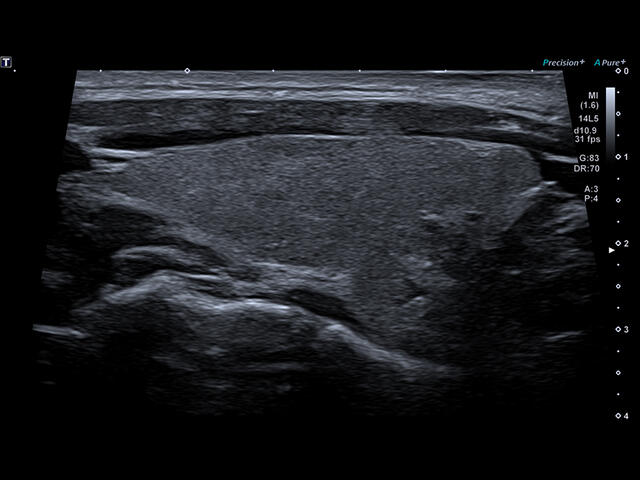

Aplio a550 – это многофункциональная УЗИ система экспертного класса. Высокое качество изображения и интуитивно понятный интерфейс поможет вам обеспечить высокую производительность и скорость проведения исследования.

Отличная цветопередача с высокой детализацией и четкостью изображения. Устройство подходит для профессионального использования в частных кабинетах и крупных медицинских центрах. Комплектация сканера применима для самых разных исследований. Широкий диапазон прикладного клинического программного обеспечения высокоэффективен для общих исследований, сердечно-сосудистых, гинекологических, ортопедических, урологических.

Aplio a550 может работать с линейным матричным датчиком и поддерживает новейшие монокристаллические датчики. Также Aplio a550 поддерживает большое количество дополнительных опций, таких как - SMI, Компрессионная эластография, Эластография сдвижной волны, Smart Fusion, исследования с использованием контраста (CEUS), 3D реконструкции в реальном времени (4D), функции автоматической оценки подвижности миокарда и фракции выброса.

- MicroPure. Высокотехнологичное решение в области выявления микрокальцификатов – маркеров новообразований злокачественного типа. Маркеры идентифицируются путем изучения затененных изображений целевого участка. Микрокальцификаты отображаются в виде белых пятен.

- SMI. Опция, упрощающая визуализацию микроциркуляторного русла. С ее помощью обследуются сосуды с низкой интенсивностью кровотока, изучаются наиболее тонкие структуры. SMI упрощает диагностику новообразований, минимизирует вероятность ошибки.